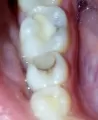

Здравствуйте, примерно 7-8 месяцев назад мне поставили пломбу на 6 верхний зуб. Недавно начала замечать, что зуб под пломбой чернеет. Может быть, что часть зуба будут удалять, или вообще весь зуб?